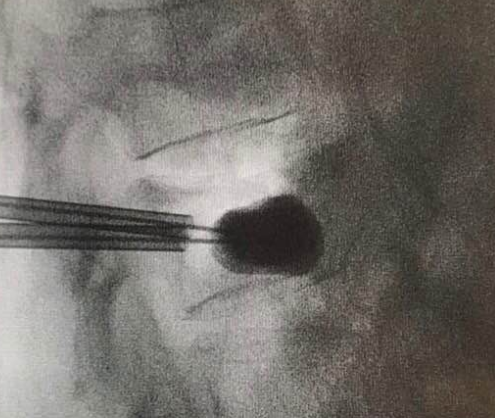

椎體成形術俗稱打骨水泥,是以針孔微創的手術,把人造骨粉(丙烯酸膠粘劑)注射到脊椎椎體骨折下陷的地方,強化並鞏固因骨質疏鬆導致脆弱的骨骼,重建椎體的骨骼形狀以防止下陷前傾的骨椎進一步惡化(見圖二至五)。適合進行椎體成形術的情況包括(1)因骨折造成的持續腰背痛;(2)因嚴重骨質疏鬆致骨骼脆弱,脊骨前傾及出現駝背現象;(3)任何藥物都起不了作用。這項小手術只須一小時的時間,病人可在術後24小時回家,不須再服止痛藥,但須服用抗骨質疏鬆藥物,來預防脊椎、盤骨或其他部位骨折及下陷。

椎體成形術是以針孔微創的手術,注射人造骨粉(丙烯酸膠粘劑)到脊椎椎體